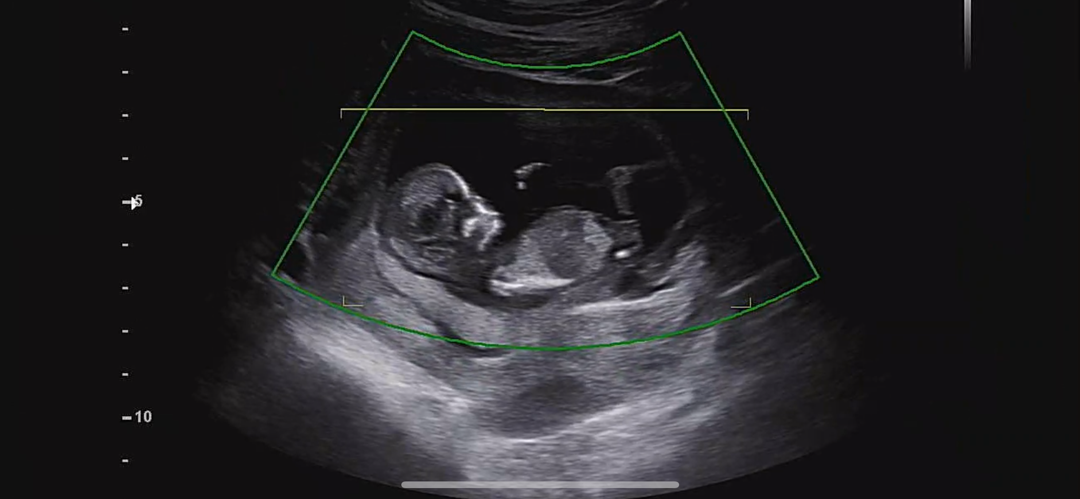

12주1일차 각도법 부탁드려요 !!

안녕하세요 오늘 1차기형아 검사 보러갔구 각도법 궁금해서 사진 올려봐요 의견 부탁드려요 !!